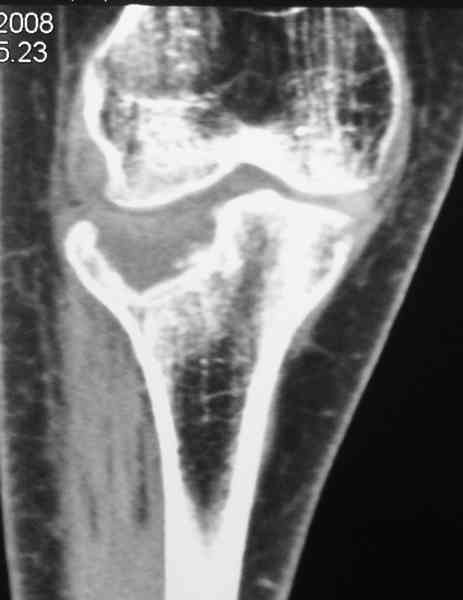

Уважаемый Абдурашид. Если нет противопоказаний , то из оперативных способов, я бы рекомендовал следующие: Полное замещение наружного мыщелка аллотрансплантатом либо открытая репозиция с элевацией и замещение дефекта ауто или аллокостью. В Ваших условиях , я бы рекомендовал второй способ. Во-время элевации необходимо разъединить фрагменты со стороны сустава ( надсечь скальпелем по линиям перелома, а затем тонким остеотомом их разъединить. При помощи долота произвести неполную остеотомию ( захватите не менее 1,5 - 2 см губчатой кости и поднять фрагменты, визуально отрепонировать и фиксировать 2-3 спицами. Дефект заместить костным ауто или аллатрансплантатом. Окончательная стабилизация пластиной ( лучше с угловой стабильностью, либо АВФ - позволит спокойно устранить угловую деформацию.

Недавно поступила больная через 1,5- 2 месяца.